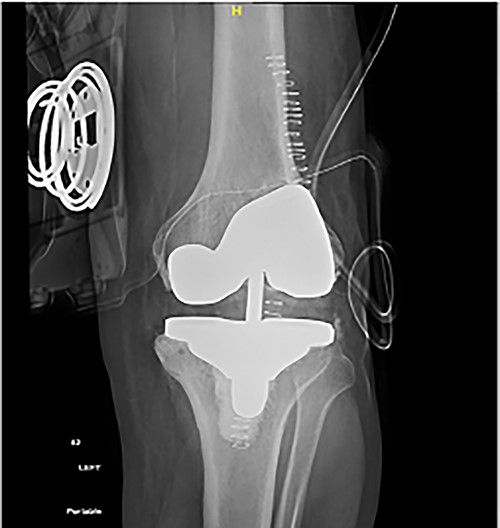

Post-operative plain radiographs from follow-up visits; (A) 3-month post-operative AP radiograph showing implant in place with a lateral gap sized to be 3.2 cm; (B) 3-month post-operative lateral radiograph of the knee showing implant in a satisfactory position.